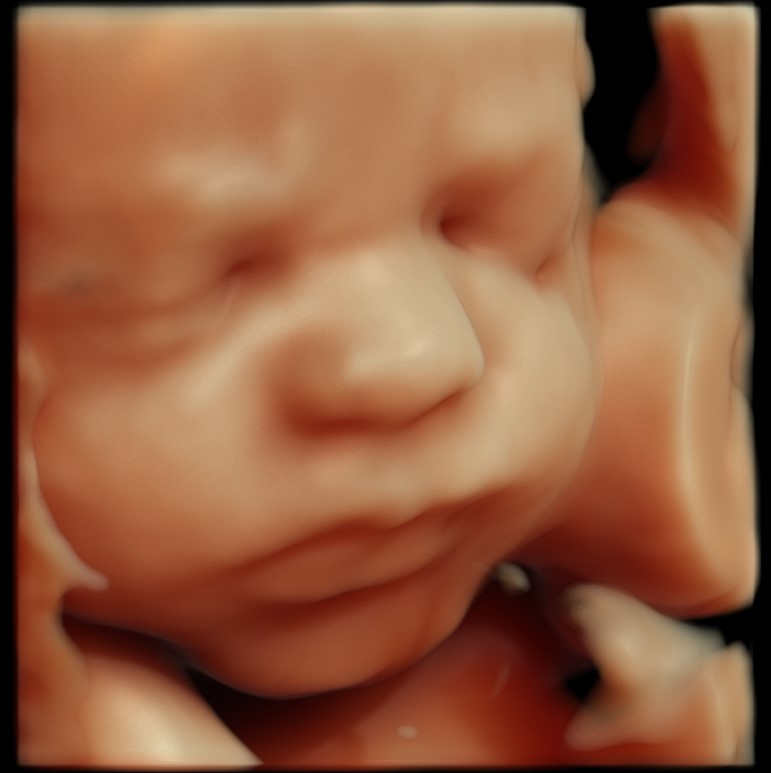

Kvalifikovaný personál, len tá najlepšia skúsenosť. Vyšetrenie pani doktorky bolo vysoko profesionálne, s osobným prístupom, slovným popisom jednotlivých úkonov počas celého procesu, zrozumiteľným vysvetlením výsledkov, a poskytnutím odporúčaní či odpovedí na všetky naše otázky. Môžem len odporúčať.